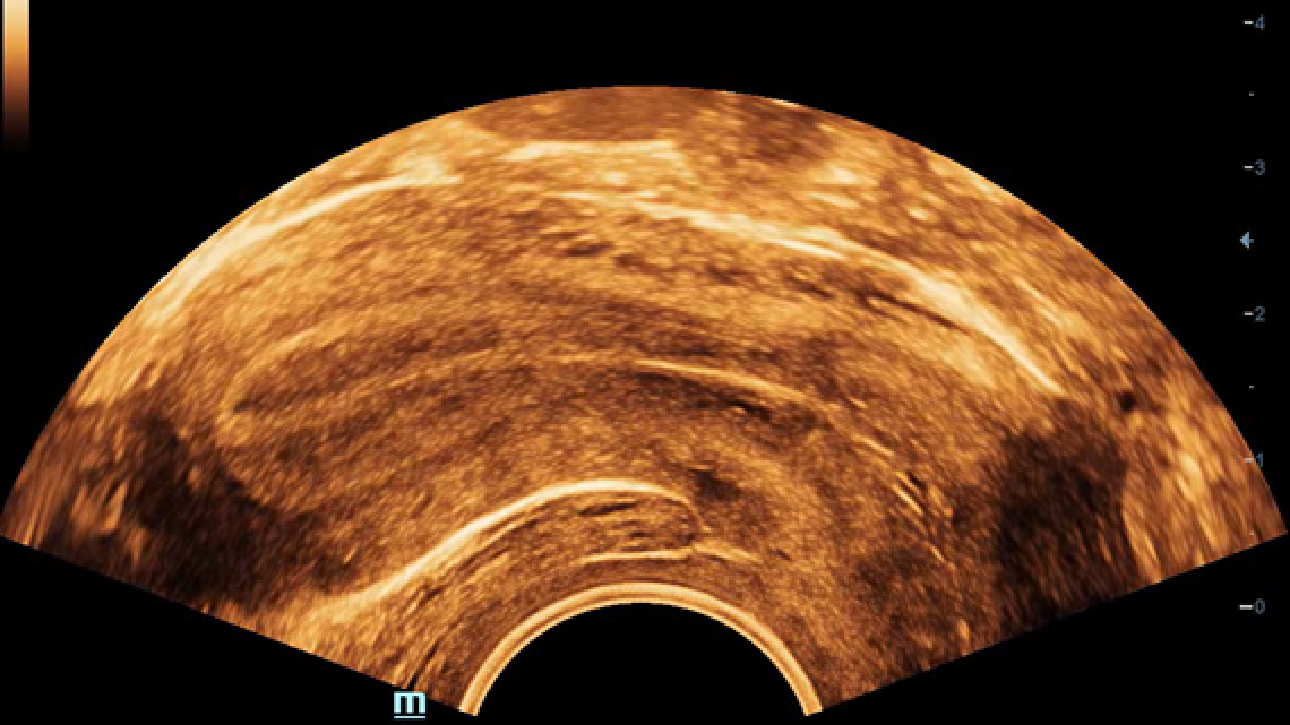

ImĂĄgenes clĂnicas